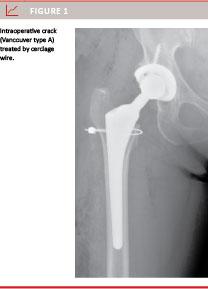

A total of 85 fractures were seen in the 3,295 patients (2.6%). A total of 2,408 of the patients had an uncemented femoral component with a fracture rate of 2.9% (69 patients). Forty-one of the 69 fractures in uncemented THAs were intraoperative cracks (Vancouver type A) which were usually treated with cerclage wires during the index operation (Figure 1). In 28 of the 2,408 uncemented cases (1.2%), a “new” type of fracture was seen. Immediate post-operative radiographs on the second or third day were normal, but seven (median) and 14 days (average) post-operatively, a sudden pain in the thigh without any trauma was experienced. Radiographs now showed a slightly displaced split fracture from the calcar region to the medial femoral shaft 8-10 cm below the lesser trochanter (Figure 2) with subsidence of the implant. Re-operation with exchange of the implant after internal fixation of the fracture with cables or a trochanteric grip was usually performed.